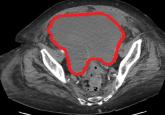

Computed tomography revealed a hematoma measuring 15 by 15 cm compressing the bladder and causing hydronephrosis.